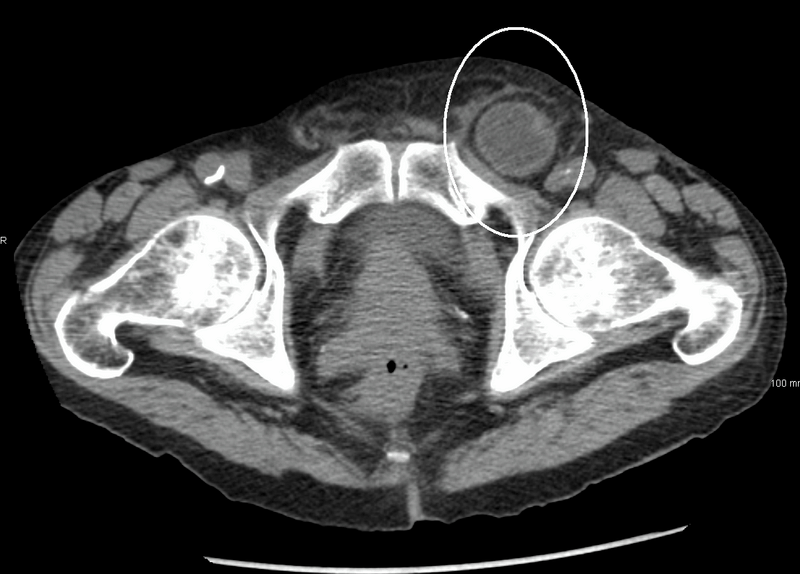

When tissue protrudes through a defect, there is a risk of incarceration and strangulation. Many pediatric hernias are reducible, where the contents can be pushed back through the defect with gentle external pressure. In most cases, the hernia can be reduced, and emergent operative management is not indicated. However, if a hernia cannot be reduced, there is concern for incarceration.2 An incarcerated hernia generally is tender to palpation with possible color change, including erythema. It then can lead to strangulation, where the blood supply to the contents becomes compromised. This process can occur in as little as two hours from the time of incarceration. The ischemic herniated content will not only cause gastrointestinal compromise but also can lead to a systemic inflammatory response syndrome (SIRS). A patient with an incarcerated and strangulated hernia can present to the emergency department with bowel obstruction symptoms, such as abdominal distention, nausea, vomiting, and obstipation. When ischemia is present, the patient may have severe pain. The affected area also can develop a dusky appearance caused by the vascular compromise. It is important to recognize that a patient with a strangulated hernia can present with peritonitis, hematochezia, and shock. See Figure 2 for imaging of an incarcerated hernia.

Figure 2. Incarcerated Hernia on Computed Tomography |

Source: Heilman J. Inquinalhernia. Wikimedia Commons. Published June 2, 2011. https://commons.wikimedia.org/wiki/File:Inquinalhernia.png. CC BY-SA 3.0. |